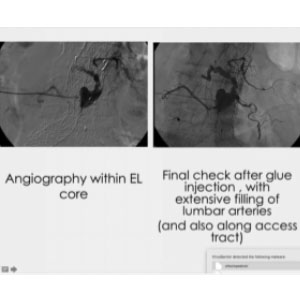

Here we first opted for coils, but six months later, we realized the leak was still there. We navigated through a large network of collateral branches and injected a glue that was diluted enough to navigate even further, along the lumber arteries, close to the aorta. In this way, starting from one single spot on the right side, we were able to reach both sides, right and left.